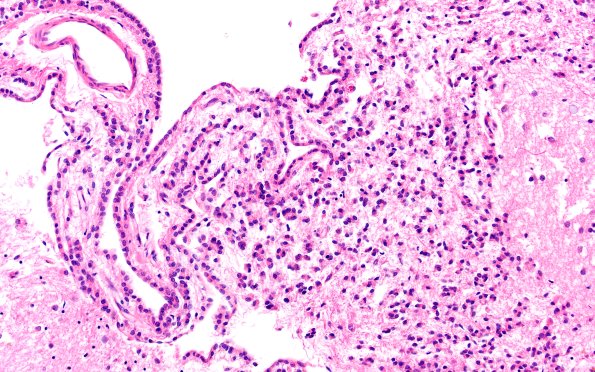

Washington University Experience | NORMAL | Ependyma | 10A3 Ependyma, lateral ventricle (Case 10) N2 20X

Increasing magnification images of the lateral ventricle wall overlying the caudate nucleus containing large numbers of dissociated ependymal cells. (H&E)